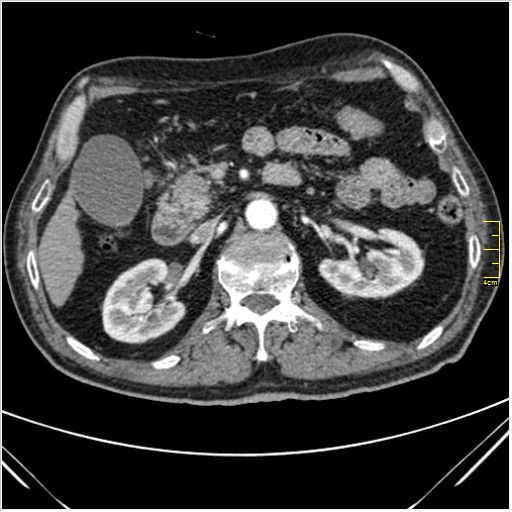

Мужчина 62 года с желтухой

Опухоль головки поджелудочной железы, расширение холедоха и панкреат. протока (Double Channel sign)

Карциномы панкреас гиподенсны на КТ с болюсом, т.к. содержать много соединительной и фиброзной ткани, в отличие от нормальной ткани железы, которая (как любая железа) хорошо васкуляризирована. Поэтому если видим в панкреас солидное гиподенсное образование - всегда настораживает на предмет рака. Второй момент: обязательная оценка взаимоотношения опухоли к ВБА и ВБВ, на предмет оценки операбельности.